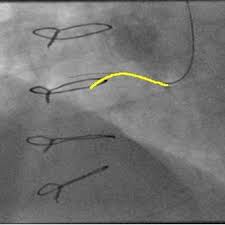

We present a method to track vessels in angiography. The vessel tree tracking problem is solved using an efficient dynamic programming algorithm.

@article{vesseltree2017,title={Vessel Tree Tracking in Angiographic Sequences},author={Zhang, Dong and Sun, Shanhui and Wu, Ziyan and Chen, Bor-Jeng and Chen, Terrence},year={2017},journal={Journal of Medical Imaging (JMI)},volume={4},number={2},pages={025001},}

We model the wire-like structure as a sequence of small segments and formulate guidewire tracking as a graph-based optimization problem.

@article{guidewire2016,title={Guidewire Tracking Using a Novel Sequential Segment Optimization Method in Interventional X-Ray Videos},author={Chen, Bor-Jeng and Wu, Ziyan and Sun, Shanhui and Zhang, Dong and Chen, Terrence},year={2016},journal={IEEE International Symposium on Biomedical Imaging (ISBI)},}